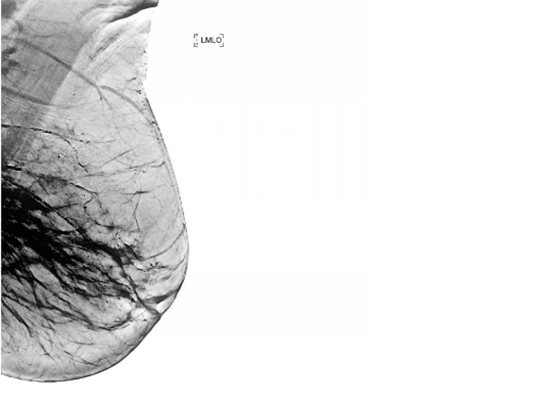

Этот цикл я писал, всматриваясь в медицинские снимки умирающего родного тела. Я пытался разглядеть его изнутри и осознать неосознаваемое: как это — постепенно умирать? Как отпустить, чем отстоять и куда его уложить, чтобы не было больно? В ужасе я наблюдал за расплывающимися узорами смерти, пока она не залила все живые уголки дряхлого тела. Снимки и тексты — свидетельства скрытого, немого страдания, которому я даю право быть увиденным и услышанным.

Это — кадиш по моей бабушке, которая умерла 18 января 2019 года. Была пятница, и похоронить ее нужно было до захода солнца — до начала Шаббата, который наступает в пятничный вечер. Кладбище было напротив больницы, через дорогу. Мы хоронили ее через три часа после смерти, не успев позвать ни родных, ни близких. Кадиш — это иудейская поминальная молитва. Для ее чтения необходим миньян — десять мужчин. Нас было меньше, поэтому хоронили без молитвы, спешно. Эти стихотворения — мой кадиш, который тогда мне произнести не дали, мое отпевание пустоты, что осталась после нее. В кадише использованы реальные медицинские материалы — рентгеновские снимки, УЗИ, КТ, ЭКГ — из истории болезни бабушки, с момента обнаружения рака и до самой смерти. Последняя кардиограмма была снята с мертвого тела. Так требовал больничный протокол.